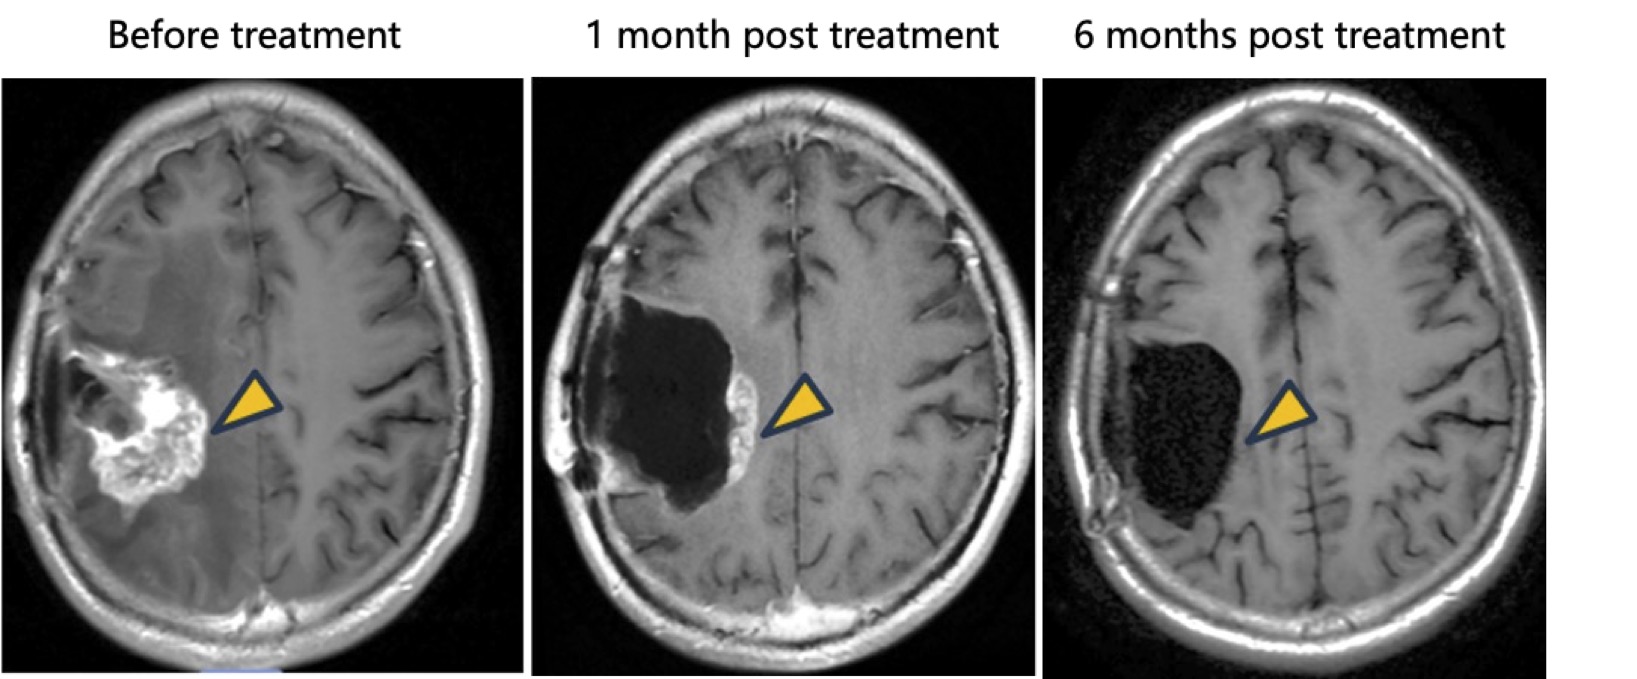

Complete Response: In one patient receiving tumor resection followed by intracavitary NXL-004 injection, postoperative imaging showed progressive tumor reduction, ultimately resulting in complete radiographic disappearance, achieving a complete response (CR).